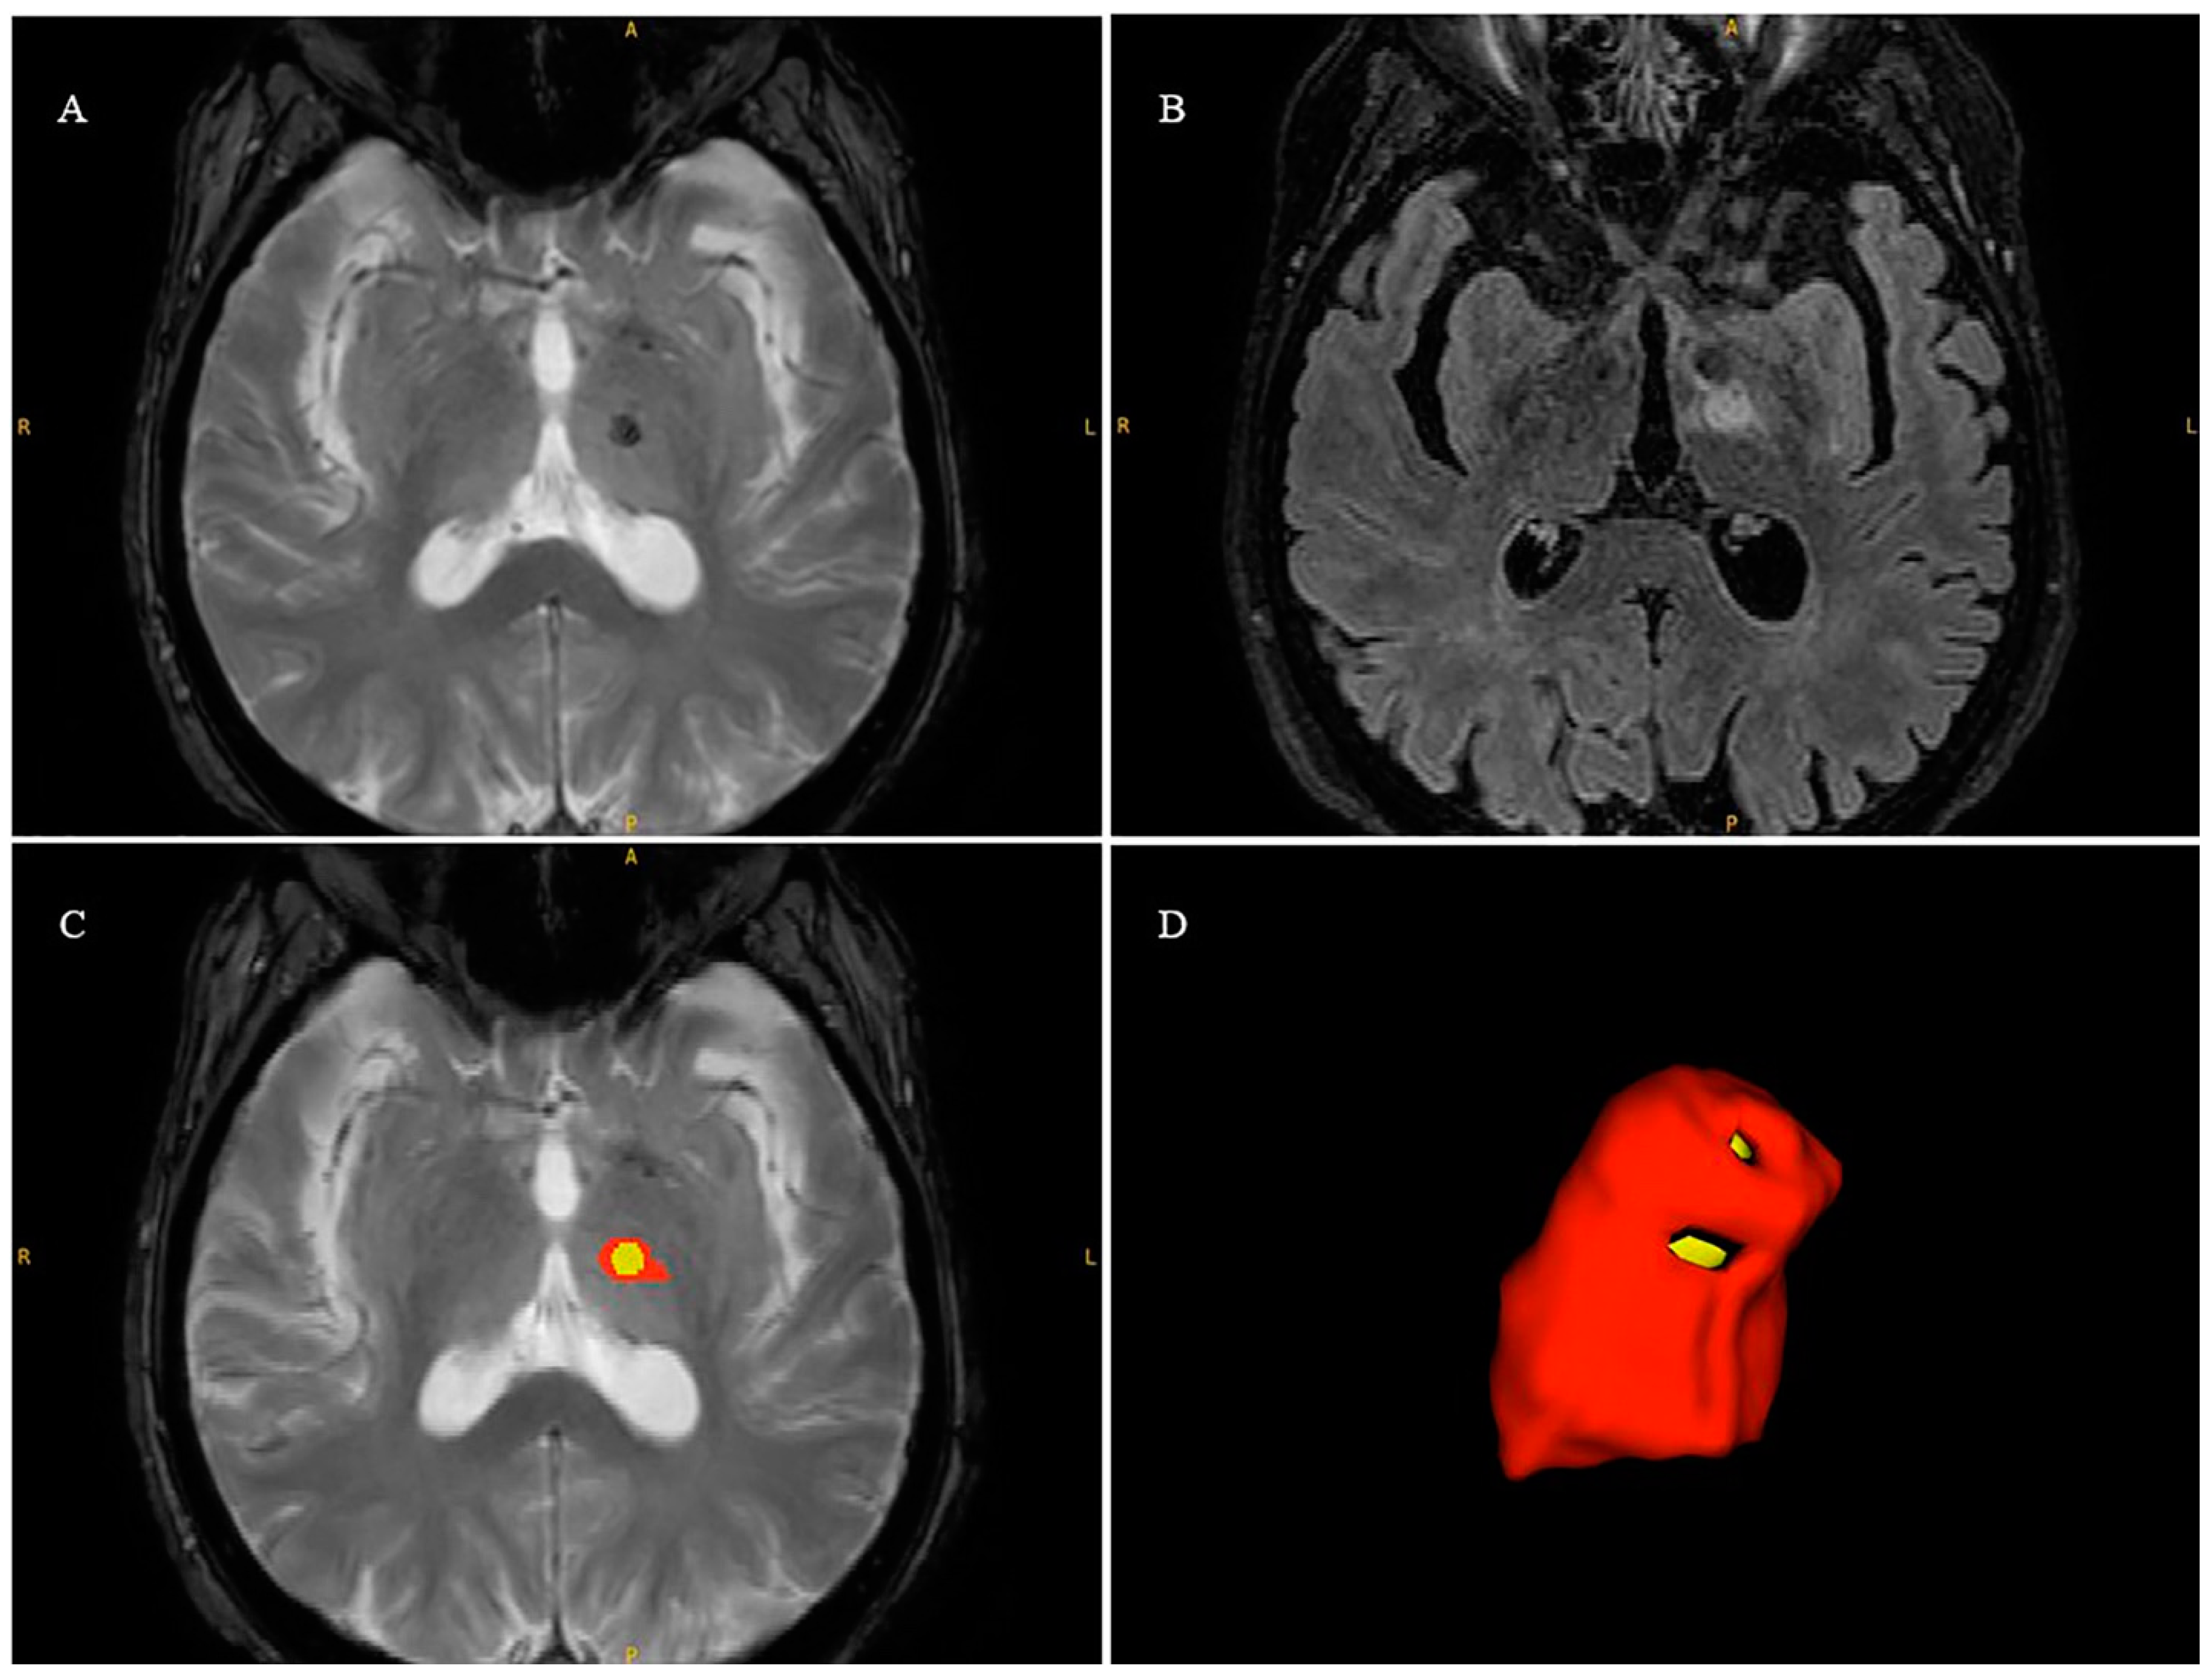

| I° Rater | II° Rater | ICC | Mean Dice | |

|---|---|---|---|---|

| Edema Volume (cm3) | 1607.24 ± 705.5 | 2042.76 ± 895.92 | 0.81 | 0.74 ± 0.13 |

| Necrosis Volume (cm3) | 179.31 ± 135.72 | 153.35 ± 118.56 | 0.88 | 0.70 ± 0.11 |